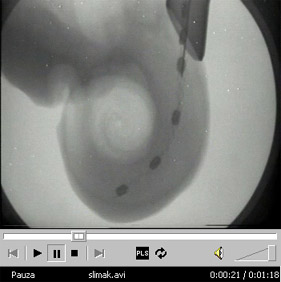

Kliknij aby obejrzeć prezentację o umieszczaniu elektrod wewnątrz ślimaka [5,75MB]

Prezentacja przedstawiająca umieszczanie elektrod wewnątrz ślimaka ( ściągnij [5,75MB] )